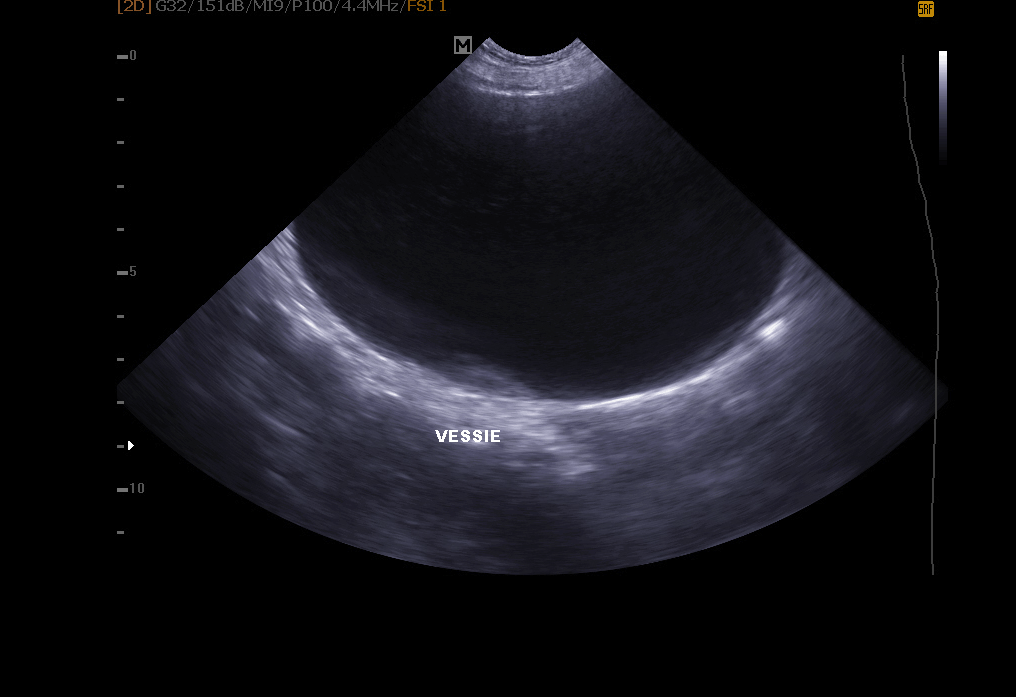

Abdomen-Ultraschall: ermöglicht die Untersuchung der Blase (Suche nach Steinen, Polypen, Tumor), Nieren, Milz, Leber, Bauchspeicheldrüse und anderen Bauchorganen.